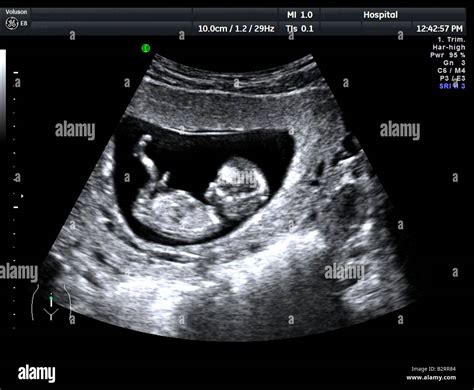

Eine Schwangere in der 28. Schwangerschaftswoche berichtet von einer milden COVID-19-Erkrankung mit Fieber und Erkältungssymptomen. Nach der Infektion wurde bei einer Ultraschalluntersuchung eine Beeinträchtigung der Plazenta festgestellt. Dennoch entwickelte sich das Kind zeitgerecht und schien ausreichend versorgt zu sein. Die Ärztin empfahl eine erneute Kontrolle nach dem Urlaub, was von der Schwangeren als unsicher eingeschätzt wurde.

Es wird auch darauf hingewiesen, dass dunkle Flecken auf dem Ultraschall eher ein Hämatom als eine Verkalkung darstellen und sich zurückbilden können. Die direkte Kausalität zwischen COVID-19 und einer verkalkten Plazenta wird in Frage gestellt, da solche Diagnosen auch schon vor der Pandemie existierten.

Bei einer COVID-19-Infektion während der Schwangerschaft ist es ratsam, engmaschige ärztliche Kontrollen wahrzunehmen. Eine frühzeitige Untersuchung der Plazenta mittels pränataler bildgebender Verfahren kann helfen, mögliche Beeinträchtigungen des Fötus zu erkennen und gegebenenfalls Maßnahmen zu ergreifen.